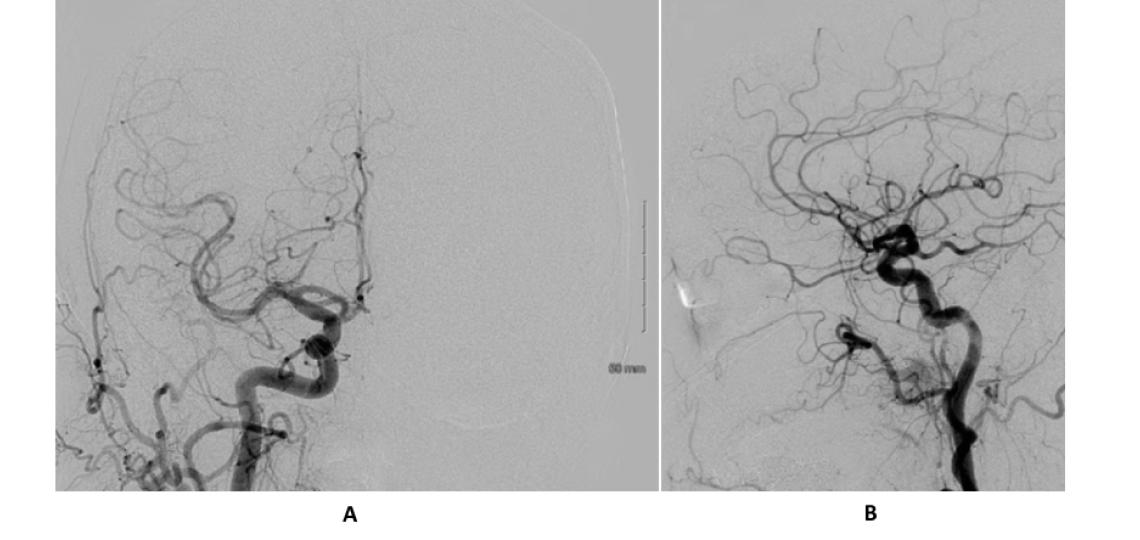

Right common carotid injection (A) shows an irregular lingual artery as the source of bleeding (arrow). The lingual artery no longer fills on the post-embolization angiogram (B).